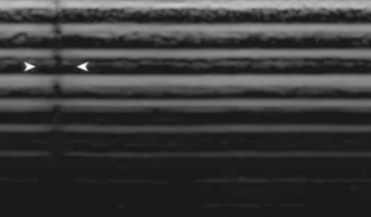

Faulty Elements

Piezoelectric crystals may become damaged or breaks in wiring can occur

Displayed as anechoic vertical lines

To confirm:

Use more gel

Change approach

Use on various patients

Confirmed if still appears in exact location